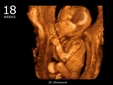

• 18. Hafta: Fetüs, yaklaşık 15 cm uzunluğundadır. Anne adayı, daha fazla rahatsızlık hissedebilir.